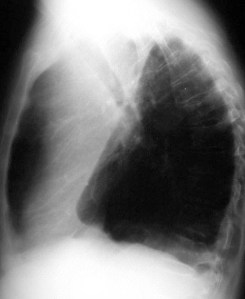

SIGNO DEL ARCO AÓRTICO OCULTO

En la radiografía lateral de tórax, se ha descrito que la ausencia de la imagen del arco aórtico puede ser la clave diagnóstica de coartación aórtica. La imagen izquierda muestra el signo. Se trata del mismo paciente del Signo de las muescas costales (ver Otros signos de pleura/pared). La imagen derecha corresponde a una radiografía normal con la sombra aórtica visible (flecha).

Se han propuesto varias explicaciones para este signo; puede ser debido a hipoplasia del arco aórtico combinada con la coartación, a dilatación de las arterias braquiocefálicas (particularmente la arteria subclavia izquierda) que oscurecen el margen superior del cayado, o a hipoplasia y desplazamiento anteromedial de la porción distal del arco aórtico.

Este artículo de Chen es la referencia: Obscured aortic arch on the lateral view as a sign of coarctation. Radiology 1984: 153; 595-596.